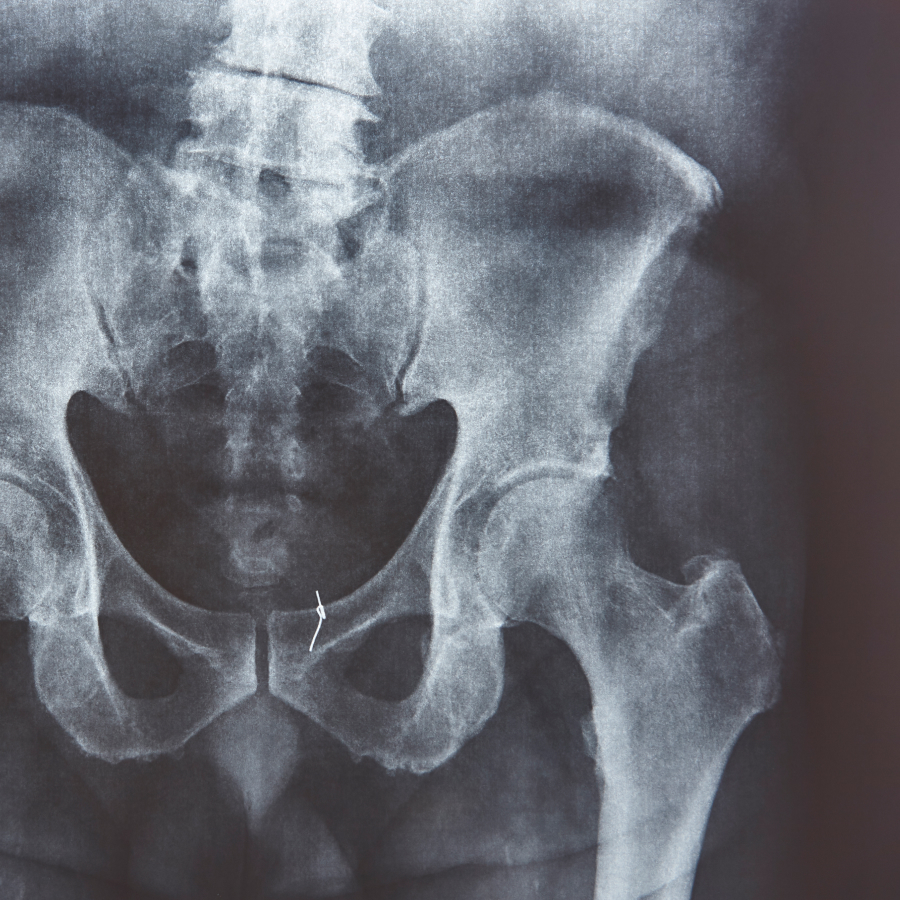

Cadera